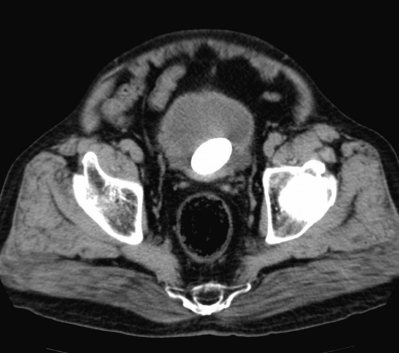

尿所見:蛋白2+、糖(-)、潜血3+、沈渣に赤血球多数/1 視野、白血球多数/1 視野。腹部エックス線写真と腹部CTとを別に示す。尿培養を提出して抗菌薬の投与を開始した。